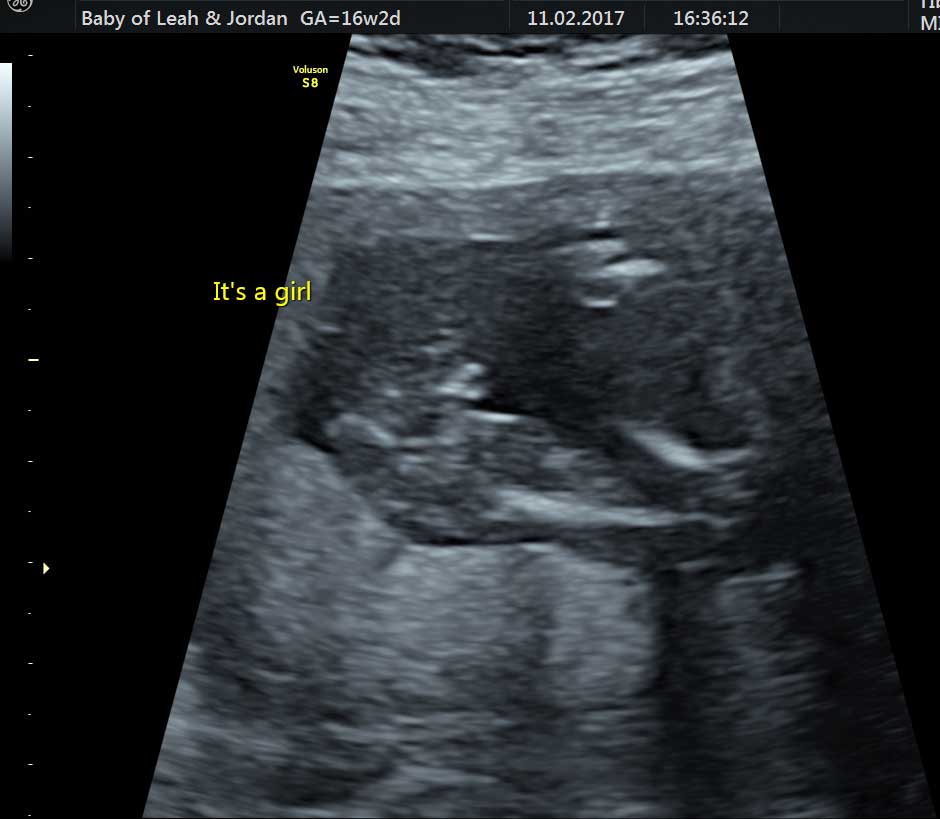

The scan was amazing. It was so clear. First, we were shown baby’s little heart beating and they let us hear it. The Sonographer then had a look between baby’s legs to have a peep at what gender baby is. We are having a little girl! It was so emotional to have our families there at that moment – seeing my mum burst into tears was the icing on the cake – she never cries! We got to see baby in 4D which was incredible. Although baby is so small, we could see her tiny nose and fingers! There are no words to describe the feeling that scan gave us.

“We are having a little girl!”